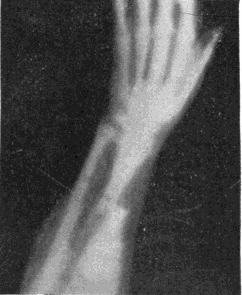

Fig. 2.—Broken Arm, Overlapping.

(Due to defective setting.)